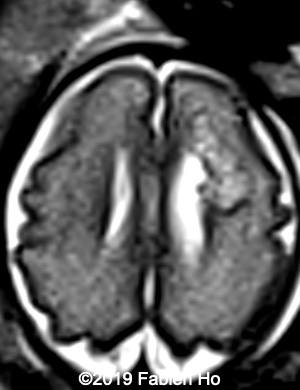

Images 4-11, fetal brain MRI at 28 weeks: the left frontal lesion hence shows DWI hyperintensity, with T2* and T1 peripheral hyperintensity: ischemia with peripheral subacute hemorrhage. Note also that there is an associated blood clot in the left lateral ventricle. There is no obvious mass effect, nor peripheral edema. All these findin>gs are very suggestive of a clastic lesion.

Axial DWI (diffusion weighted imaging): DWI is sensitive to cytotoxic cell edema, found in brain ischemia, among other things.

10

11

Our diagnosis was hence fetal stroke: probably ischemic stroke with secondary hemorrhagic transformation (hemorrhagic stroke could also be a possibility although the absence of mass effect and central lucency without hemorrhagic signal make this hypothesis less likely). Besides, in most pediatric and fetal clastic lesions, hemorrhage and ischemia are associated.